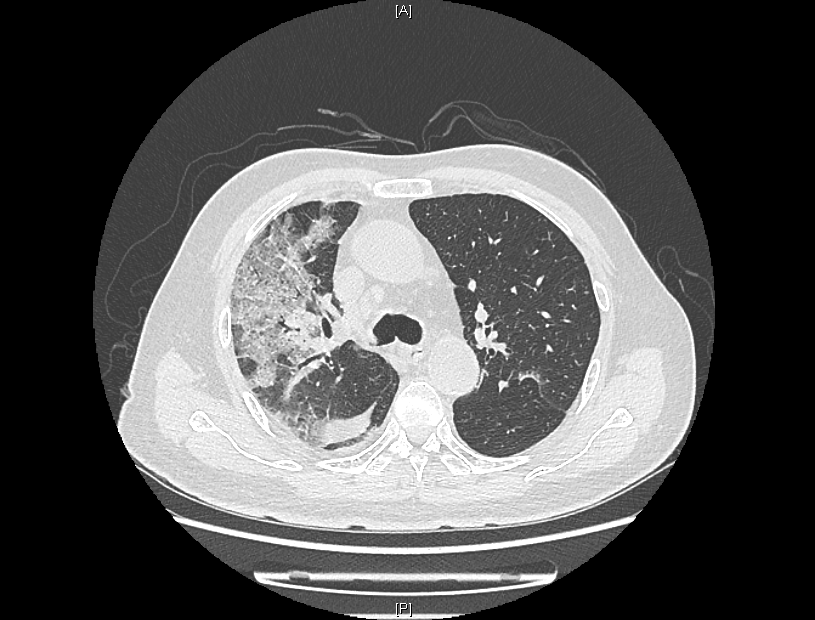

来院时,患者感染新冠病毒5天,持续发烧不退,出现了憋气、意识不清。入院后持续监察发现,患者肺部CT逐步呈“白肺”状态,血气氧分压一度降至50mmHg,“正常血气氧分压为80-100mmHg,低于60mmHg,在临床上就可诊断为I型呼吸衰竭。”感染性疾病科主任林明贵说。同时,患者合并长年慢阻肺、高血压病史,以及少见的血液病单克隆丙种球蛋白病、心梗病史、甲状腺功能减退、肾动脉狭窄等疾病。

患者肺部CT检查图像

在多学科联合保驾之下,老人入院后5天病情出现了转机,成功解除无创呼吸机,并逐步从高流量吸氧降至经鼻导管吸氧。“当时看到肺部影像时,心已经凉了半截,做好了最坏的思想打算。”患者的儿子说,老人生病前爱好打乒乓球,希望此次康复后,重新回归他热爱的球场。